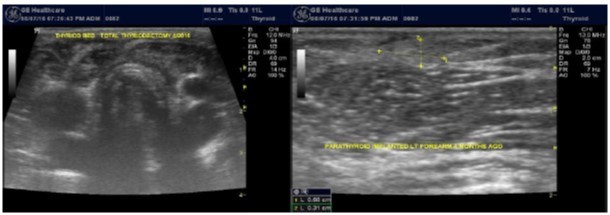

Any nodule with intermediate indeterminate cytology or higher on FNA should go to surgery 23. Among our patients population, one patient with nodular pathology and tertiary hyperparathyroidism was found to have papillary carcinoma of the thyroid during parathyroiectomy. Total thyroidecotmy was done and the patient got forearm implantation of one of the parathyroid glands, Figure 6.

Figure 6.Total thyroidecotmy and forearm implantation of the parathyroid gland

In our study many patients were found to have nodules look very much like PT adenoma, Figure 7 below. At least, 4 patients were subsequently confirmed to have parathyroid adenomas, Figure 8 and 2 patients underwent surgery

Figure 8.Nodule that proven to be a parathyroid adenoma, volume =5265 mm3